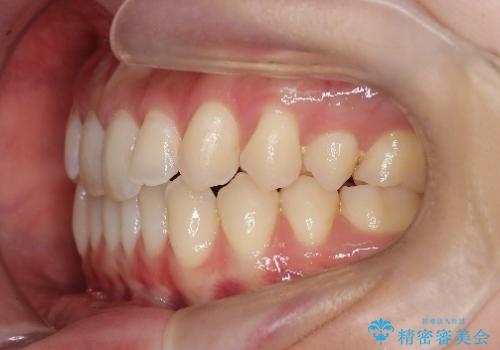

再矯正 前歯のガタツキをマウスピース矯正で治療したい

- 前に矯正治療をしたが、後戻りしてガタツキが出てきたので、治したいとのことで来院されました。

ワイヤー治療とマウスピース矯正、2通りの治療を提案させていただき、マウスピース矯正治療を希望されましたので、インビザラインによる治療を開始しました。